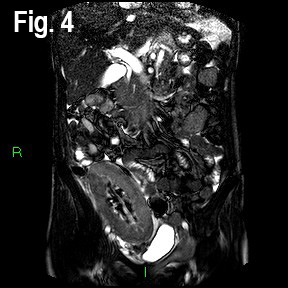

A Magnetic Resonance Angiogram (MRA) showed a low cortical signal and non-enhancing cortex post intravenous Gadinolinium administration, but no renal artery or vein thrombosis or stenosis (Fig 4 & 5).

Fig 4: Coronal images Balanced Turbo Field Echo (BTFE) MR sequence images demonstrating subtle low signal in the inner cortex.